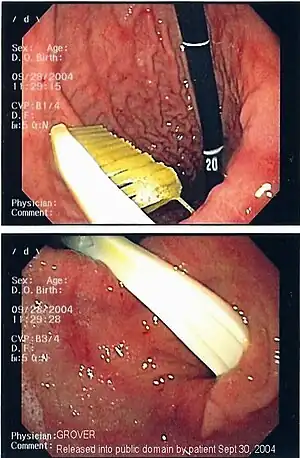

| Endoscopy image of foreign body in the stomach (toothbrush) | |